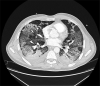

[Viral pneumonia. COVID-19 pneumonia]